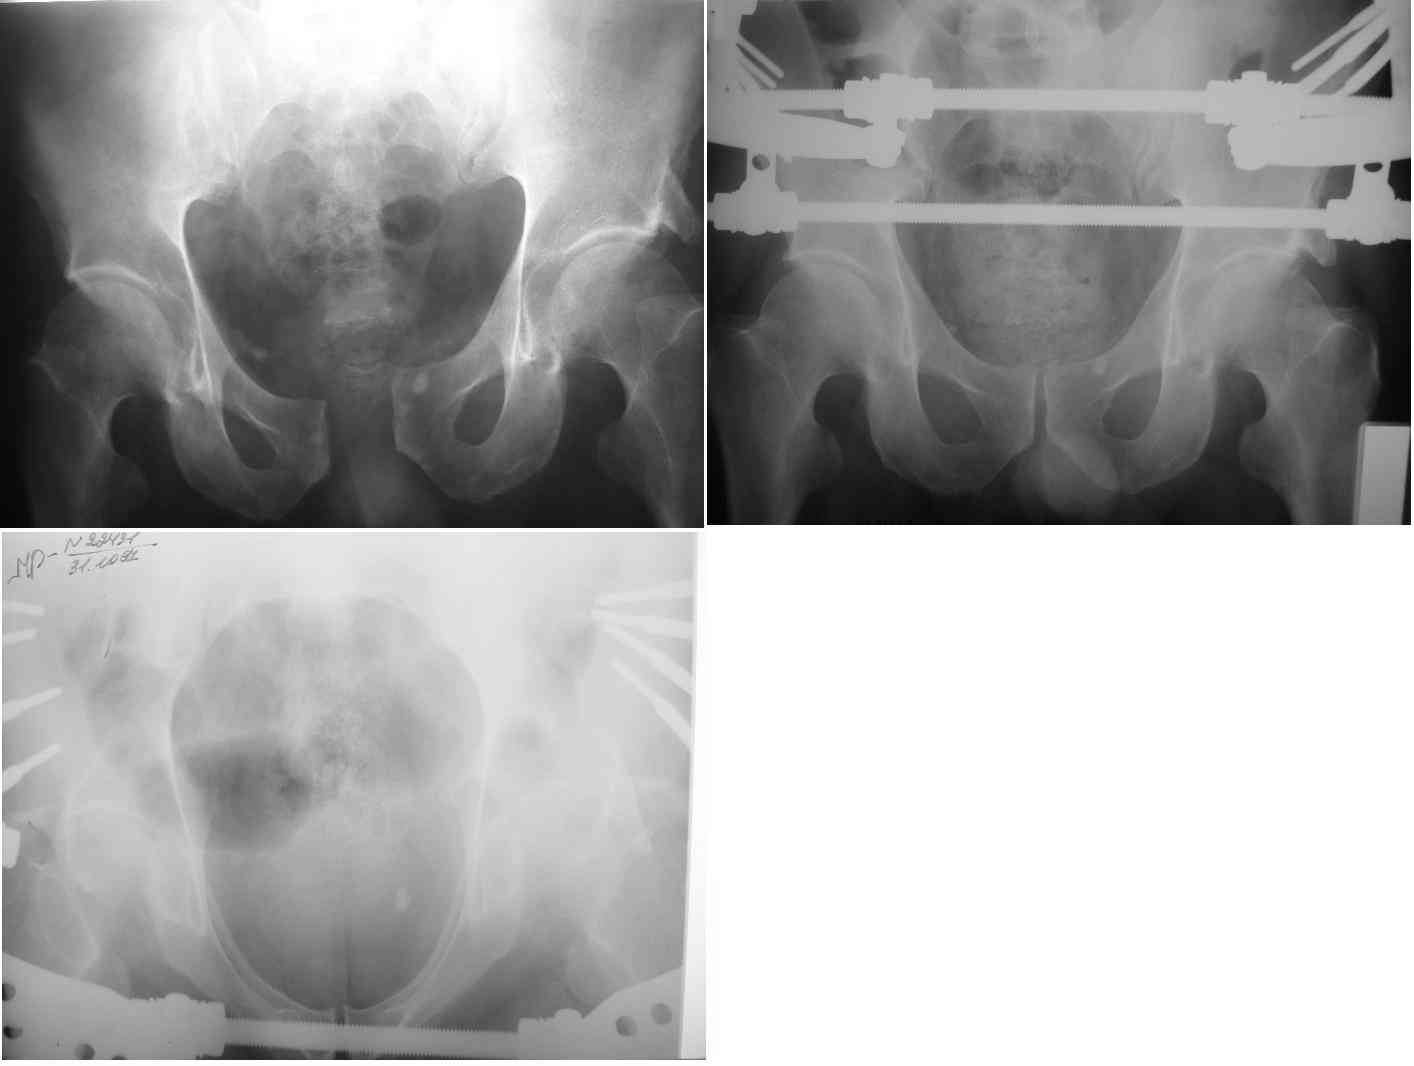

Re: разрыв лонного сочленения

извините за опоздание , вот фотографии

Репозиция действительно очень неплохая, но чтобы уменьшить риск развития поздней нестабильности, в такой ситуации лучше выполнить синтез лонного сочленения пластиной и оставить аппарат месяца на 2.